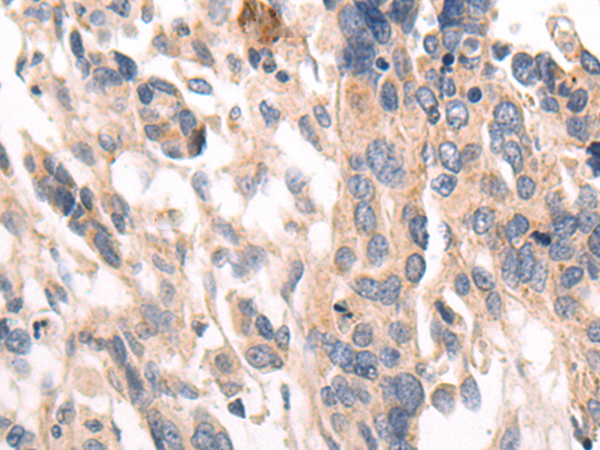

分类: 科研抗体货号: P07795别名: CCP2应用: WB,IHC反应种属: Human